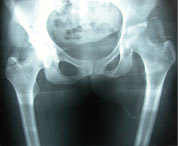

Fibrous ankylosis both hips post infection